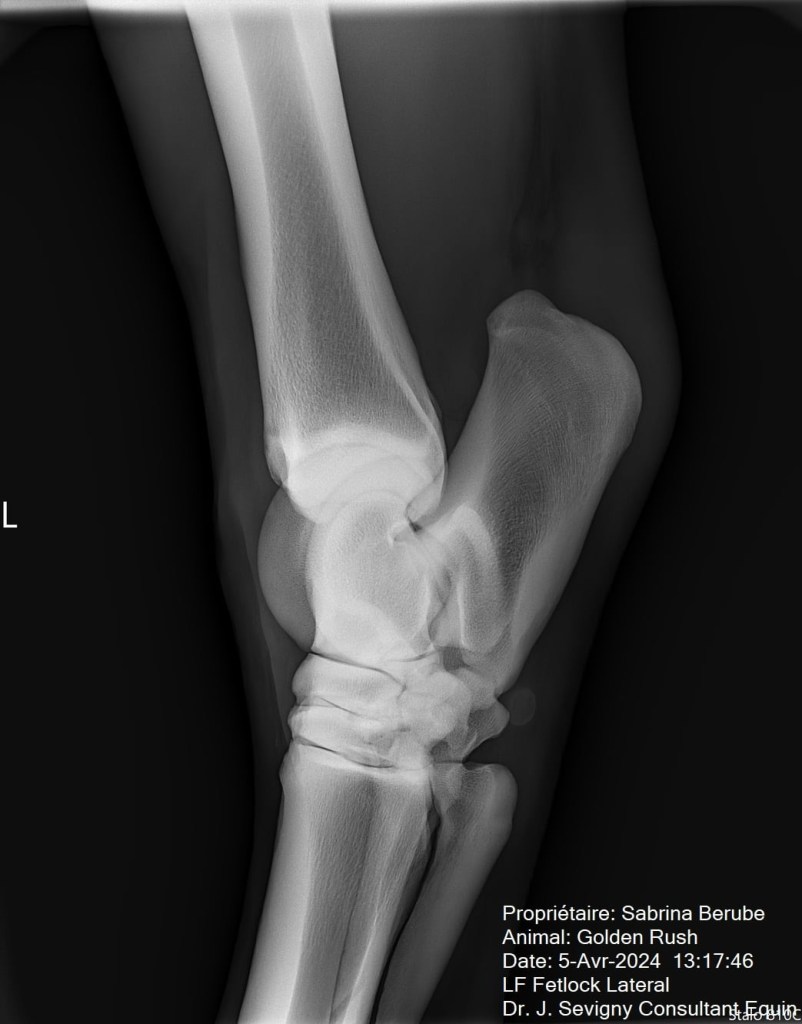

Par la suite, lors de la visite de ma vétérinaire, on a pris des radios de ses jarrets suite à son examen. Il n’a pas répondu tant que ça aux tests de flexion, mais tout de même il y a avait un petit quelque chose. Sur les radios, on a pu constater une présence d’arthrose modérée, ce qui venait expliquer le tout. Rien de surprenant vu son âge et sa discipline par contre, ce qui m’a rassurée un peu, mais je voulais traiter le problème. Je vous laisse les images pour vous donner une idée, je ne suis pas une experte en lecture de radio mais en gros, les espaces dans l’articulation sont sensés faire toute la longueur de l’articulation, mais dans le cas de mon cheval (surtout son jarret droit), l’arthrose est présente et fusionne les parties de l’articulation ensemble.